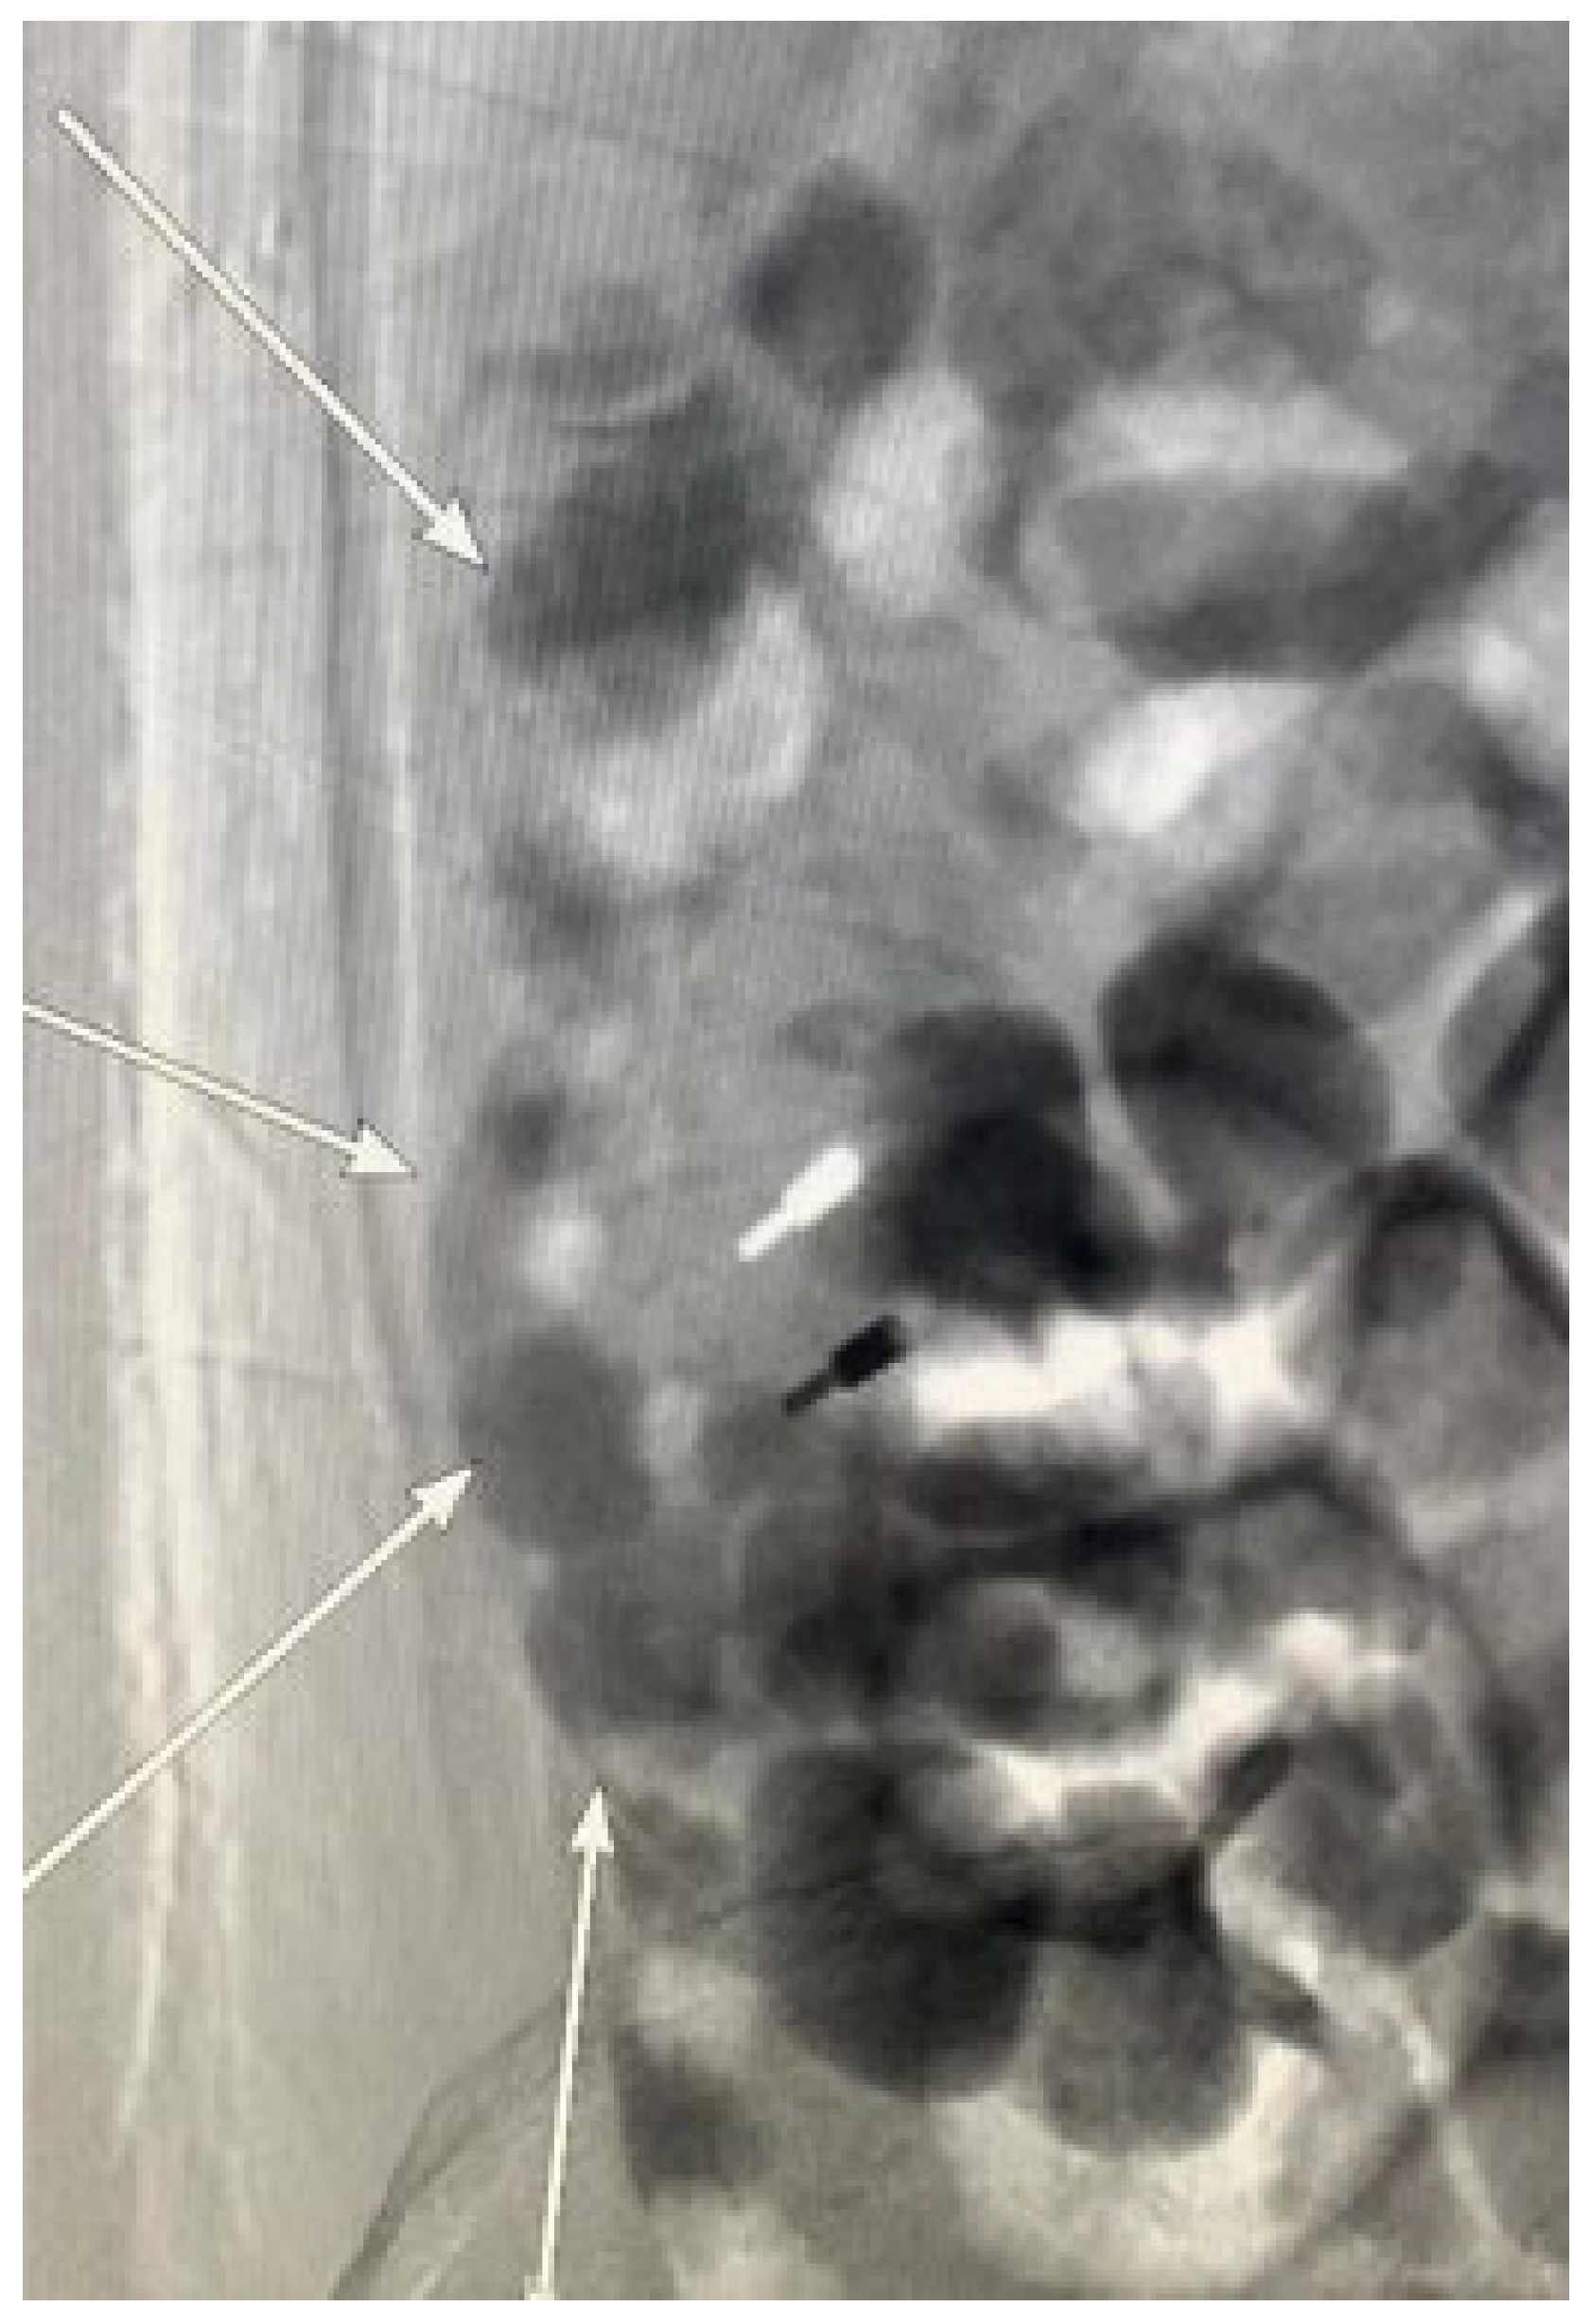

Diagnosis algorithm for ectopic variceal bleeding in portal hypertension (* Other information: Any relevant details, including the patient’s medical history). Currently, there is no consensus in the academic community on the diagnosis of ectopic varices. Therefore, the authors propose a stepwise diagnostic approach. Symptom-based assessment of bleeding origin determines the sequence and approach of endoscopic screening [12]. When there are no signs of active gastroesophageal variceal bleeding to account for circulatory failure, worsening anemia, dark red bloody stools, increased bowel sounds, and elevated blood urea nitrogen, suspicion of lower gastrointestinal bleeding should be immediately considered. Performing timely enhanced CT or enhanced MRI with targeted colonoscopy during the initial visit could have facilitated prompt intervention and stopped the bleeding. Given the rarity and concealed nature of ectopic varices, identifying the precise focus of hemostasis, however, can be challenging [13]. The diagnosis of ruptured bleeding from gastroesophageal varices is typically established through the observation of specific conditions during endoscopy: active bleeding within the varices, varices overlying a platelet–fibrin plug (known as white nipple sign), or varices overlaid with blood clots without other bleeding sources [14]. In contrast, duodenal variceal bleeding, for instance, is often submucosal and located on the convex side outside the lumen, making it difficult to detect during endoscopy [15]. Invasive methods, like enteroscopy, endoscopic ultrasound, and angiography, as well as noninvasive methods, such as video capsule endoscopy, contrast-enhanced imaging techniques, Doppler ultrasound, and radionuclide scanning, may be necessary for a definitive diagnosis. Surgical intervention may be considered if other diagnostic approaches are inconclusive. Due to the limited literature, determining site-specific treatments is challenging. Each site presents unique factors, including etiology, vascular anatomy, bleeding risk severity, hepatic reserve, and other variables, requiring personalized management. Therefore, a multidisciplinary approach involving endoscopists, interventional radiologists, and surgeons is strongly recommended. This case highlights the need to consider ectopic varices as a potential cause of atypical bleeding in patients with portal hypertension. Differentiating upper and lower gastrointestinal bleeding is one of the ABCs in diagnosing gastrointestinal diseases. In clinical practice, it is crucial not to overlook the interpretation of physical examination findings and laboratory results but solely rely on empirical knowledge, such as the common occurrence of variceal bleeding in the gastroesophageal region. Neglecting these aspects, as seen in this case, can result in delayed hemostasis and unnecessary, or even harmful invasive treatments. Early detection and an increased awareness of ectopic varices can facilitate timely and appropriate therapeutic interventions, ultimately improving patient care and outcomes. For the treatment of ectopic varices in patients with portal hypertension, less could indeed be more.